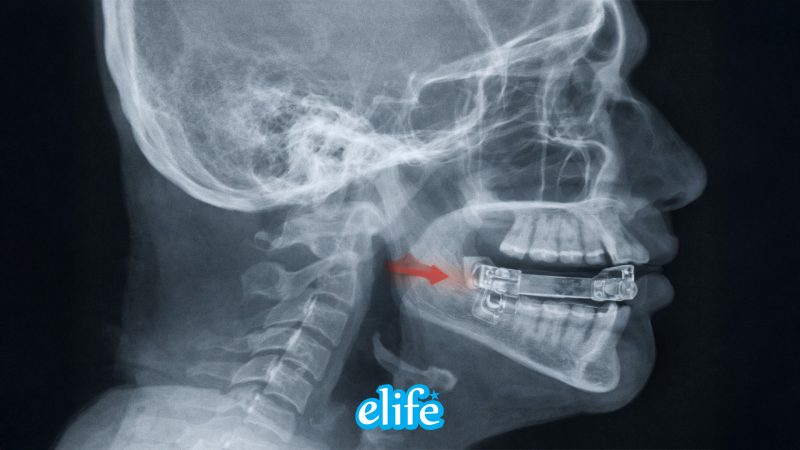

1. เครื่องดันขากรรไกรล่าง (Oral Appliance / MAD)

เป็นอุปกรณ์ใส่ในช่องปากขณะนอนหลับ ทำหน้าที่ ดันขากรรไกรล่างไปด้านหน้า เพื่อเปิดทางเดินหายใจ เหมาะกับผู้ที่เป็น Sleep Apnea ระดับเล็กถึงปานกลาง หรือผู้ที่ไม่สามารถใช้เครื่อง CPAP ได้